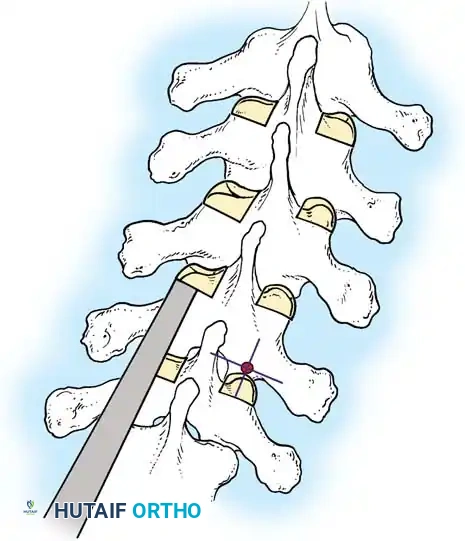

The Moe Technique (Thoracic Spine)

The Moe technique is a highly effective method for achieving intra-articular arthrodesis in the coronally oriented thoracic facet joints.

Fig. 38-26: The Moe technique of thoracic facet fusion, demonstrating the creation of hinged bone flaps.

- Expose the spine fully to the tips of the transverse processes.

- Using a sharp osteotome or Cobb gouge, begin a cut over the cephalad articular process at the base of the lamina.

- Carry this cut along the transverse process almost to its tip. Bend this cortical fragment laterally so it lies between the transverse processes, ideally leaving it hinged on its lateral periosteal attachment to preserve local vascularity.

- Thoroughly denude all articular cartilage from the superior articular process using a sharp curet.

- Make a secondary cut in the superior articular facet, working medially to laterally, producing another hinged fragment.

- Pack the resulting intra-articular defect tightly with cancellous bone graft.